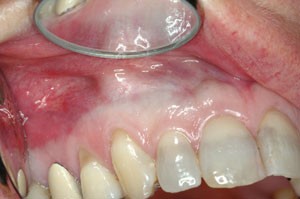

Most of the reviewed literature consisted of case reports. Thyroid cancer is frequently found with black thyroid syndrome macroscopic black discolouration of. While tetracycline and minocycline induced teeth staining or discoloration is not a significant problem with general use in the adult population it can obviously occur and result in permanent effects which can then translate into additional treatments and possible psychological and esthetic concerns for the patient. The remarkable side-effect of minocycline on the oral cavity is the singular occurrence of black bones black or green roots and blue-gray to gray hue darkening of the crowns of permanent teeth. The prevalence of tetracycline and minocycline staining is 3-6. If experienced these tend to have a Less Severe expression i.

Minocycline Side Effects Teeth. Ocular thyroid and visceral pigmentation is also relatively uncommon and usually develops only with high doses and long term minocycline use. Long term treatment with minocycline at least 100 mgday can cause hyperpigmentation of the skin nails bones thyroid teeth palate eye heart valves. If experienced these tend to have a Less Severe expression i. In contrast the oral mucous membranes and teeth are infrequently pigmented from minocycline.